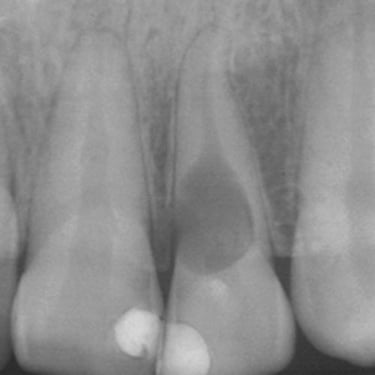

Quiste Periapical

Un quiste periapical es una cavidad llena de líquido en la punta de la raíz del diente, generalmente resultado de una infección crónica.

Los pacientes pueden notar una hinchazón sin dolor en la encía.

El tratamiento incluye el tratamiento de conducto y, a veces, la extirpación quirúrgica del quiste. Si no se trata, el quiste puede crecer y causar complicaciones.